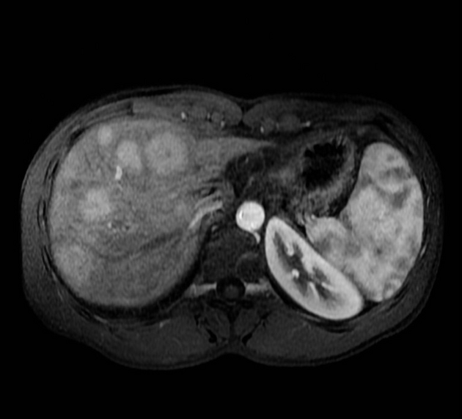

–MRI: markedly T2 hyperintense (light-bulb bright)

T2: Two rounded lesions following fluid signal seen at segment 2 and 6 of the liver.